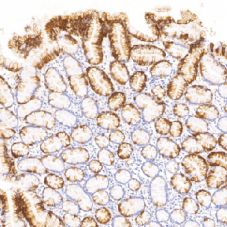

Cytokeratin 20(CK20)鼠抗人细胞角蛋白20单克隆抗体

CK20是分子量为46KD的细胞角蛋白,在正常的胃肠道上皮Merkel细胞、尿道上皮中均呈现染色阳性。主要用于胃肠道腺癌Merkel细胞癌、卵巢粘液性肿瘤的诊断,CK20多与CK7联合检测用于确定癌的原发部位。

- 阳性部位:胞质

- 适用组织:石蜡切片

- 预处理:热修复